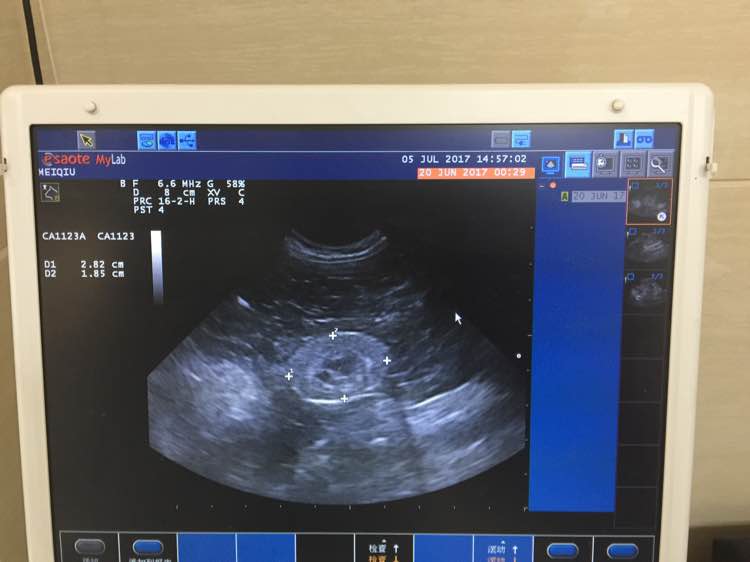

7月5日,又带孩子去复查,贫血和脱水都好了,但是肌酐又回到3开头,医生说算是很稳定了,血酸中毒也有好转,测了血压,因为不是动脉测量,所以准确率不高,需要分五次取平均值,血压带包在孩子尾巴上,前三次紧张的血压越来越高,第第四次开始我摸着他告诉他没事,就开始逐渐降下来了,平均值是高于正常值的,但医生也说觉得他并没有高血压症状,暂时高是太过紧张造成的,可以不用吃降压药,我询问了是否可以自己给孩子洗牙,医生说牙结石确实是个严重的问题,如果他要是能配合我就可以自己给他洗。